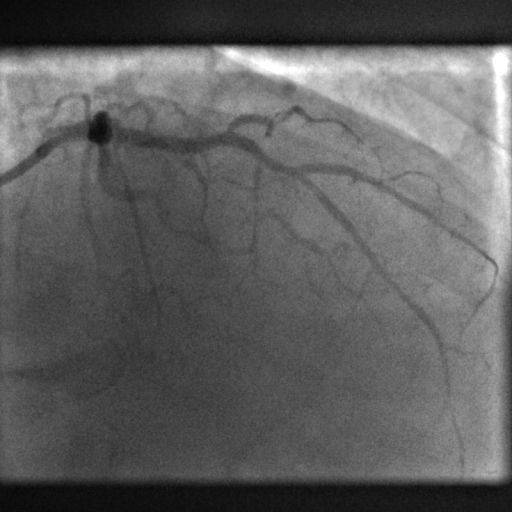

Ασθενής 79 ετών προσήλθε με προκάρδιο άλγος και ηλεκτροκαρδιογραφικά ευρήματα συμβατά με οξύ έμφραγμα προσθίου τοιχώματος.

Δόθηκε αντιαιμοπεταλιακή, αντιπηκτική και αντιστηθαγχική αγωγή και έγινε στεφανιογραφικός έλεγχος που ανέδειξε ολική απόφραξη του έντονα επασβεστωμένου προσθίου κατιόντα στο ύψος του πρώτου διαφραγματικού χωρίς άλλες σοβαρού βαθμού στενώσεις (Εικόνες 1Α και 1Β). Έγινε προσπέλαση της βλάβης σχετικά δύσκολα με σύρμα Fielder XT (Εικόνα 2). Η διέλευση μπαλονιών ήταν πολύ δύσκολη και παρά τις διατάσεις σε υψηλές ατμόσφαιρες και ρήξη μπαλονιών (grenadoplasty), η βλάβη παρέμεινε ανένδοτη. Αλλάχτηκε ο 6 F οδηγός καθετήρας σε μακρύτερο 7 F ΕΒU4.0 και προσπελάσθηκε και ο διαγώνιος κλάδος. Με την καλύτερη στήριξη, μπαλόνια πολύ υψηλής πίεσης OPN 2.5Χ10mm και 3.0Χ15mm διατάθηκαν στις 35 atm χωρίς όμως να διανοιχθεί επαρκώς η επασβεστωμένη βλάβη (Εικόνα 3). Αποφασίσθηκε η χρήση ενδοστεφανιαίας λιθοτριψίας με μπαλόνι Shockwave 3.0X12mm, το οποίο αρχικά δεν διήλθε τη βλάβη ακόμη και μετά από εισαγωγή σύρματος και μπαλονιού στην περισπωμένη για καλύτερα στήριξη (anchoring balloon, Εικόνα 4). Η διέλευση του μπαλονιού λιθοτριψίας κατέστη εφικτή μόνο μετά από χρήση προέκτασης καθετήρα Guidezilla (Εικόνα 5). Μετά την εφαρμογή και των 80 παλμών, διανοίχτηκε η στένωση και εμφυτεύτηκε stent Synergy 3.0X16mm σε υψηλές ατμόσφαιρες. Η τελική μεταδιάταση έγινε με μπαλόνι υψηλής πίεσης 3.25Χ15mm με άριστο αγγειογραφικό αποτέλεσμα και φυσιολογική ροή στην περιφέρεια.